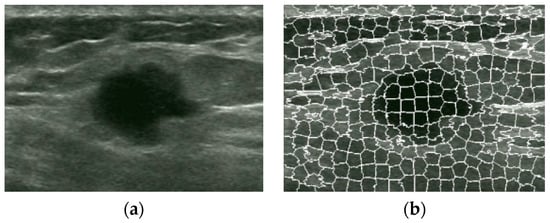

An Automatic Localization Algorithm for Ultrasound Breast Tumors Based on Human Visual Mechanism

Xie, Y.; Chen, K.; Lin, J. An Automatic Localization Algorithm for Ultrasound Breast Tumors Based on Human Visual Mechanism. Sensors 2017, 17, 1101. https://doi.org/10.3390/s17051101